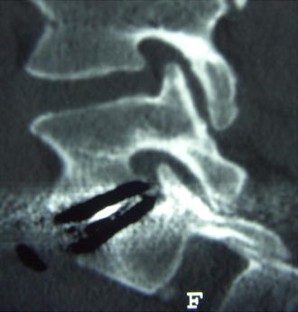

Fig. 1

Fig. 2

Fig. 3